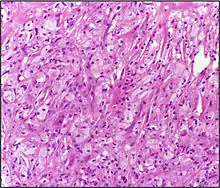

Гістопатологія

Ксантома складається з кластерів гістіоцитів з пінистою цитоплазмою внаслідок акумуляції холестеролу.